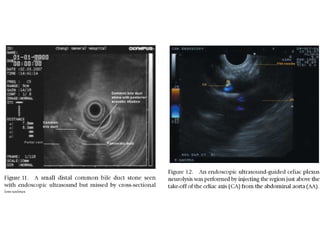

Suspected Choledocholithiasis

Choledocholithiasis

Choledocholithiasis  (cont.)

CBD   <  < STONE   <PD   HOP

<CBD stone   Duod

Injection Therapy

Celiac Plexus Block